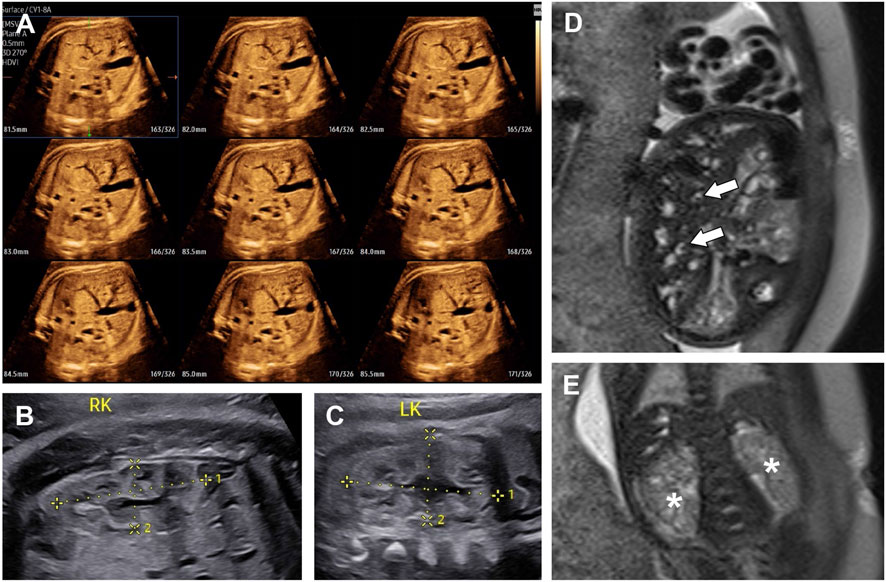

A 39-year-old woman was referred to our hospital for ultrasound consultation due to fetal hepatic anomalies detected during a routine sonographic examination. This was her second pregnancy. Her first pregnancy had ended in an induced abortion. A detailed fetal ultrasound examination at 33+4 weeks of gestation revealed multiple small tubular and cystic dilatations in the liver (Figure 1A). Both kidneys were echogenic and showed no corticomedullary differentiation (Figures 1B,C). No other abnormalities were detected.

Figure 1. The ultrasound images (A–C) and T2-weighted MRI images (D,E) of fetal abdomen at 33+4 weeks of gestation. (A) Multi-Slice view of fetal liver, showing multiple small tubular and cystic anechoic structures. (B) Right kidney (4.06 × 1.75 cm). (C) left kidney (3.88 × 2.22 cm). Both kidneys showed no obvious enlargement and loss of corticomedullary differentiation. (D) The heterogeneous liver with multiple dilated bile ducts. The central dot sign was indicated by arrows. (E) Two slightly enlarged kidneys (asterisks), showing numerous tiny cysts and no corticomedullary differentiation.

On the same day, T2-weighted magnetic resonance imaging (MRI) was performed. The dilated biliary ducts appeared as tubular or cystic hyperintense lesions on T2-weighted sequences, with the “central dot” (C-DOT) sign observed (Figure 1D). Both kidneys were slightly enlarged, with loss of corticomedullary differentiation and multiple tiny cystic lesions with hypersignal on the T2-weighted sequence (Figure 1E). After clinical counseling, the couple opted to terminate the pregnancy. As the parents declined autopsy, we were unable to confirm the presence of CHF in the fetus, and thus could not definitively distinguish between CD and CS. As a result, a diagnosis of CD/CS with ARPKD was suggested.